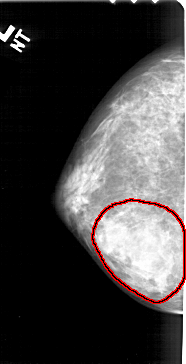

A_1379_1.LEFT_MLO

LEFT_MLO LINES 5041 PIXELS_PER_LINE 2596 BITS_PER_PIXEL 12 RESOLUTION 43.5 OVERLAY

FILE: A_1379_1.LEFT_MLO.OVERLAY

TOTAL_ABNORMALITIES 1

ABNORMALITY 1

LESION_TYPE MASS SHAPE IRREGULAR MARGINS ILL_DEFINED

ASSESSMENT 4

SUBTLETY 4

PATHOLOGY BENIGN

TOTAL_OUTLINES 1